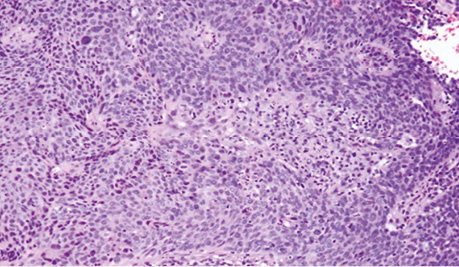

Фрагмент тканини шийки матки переважно заміщений розростаннями злоякісних епітеліальних клітин, диспластичний багатошаровий плоский епітелій через базальну мембрану поширюється в прилеглу волокнисту сполучну тканину без прикріплення до поверхні, клітини пухлини з вогнищевим плеоморфізмом, наявні фігури мітозів, некрози відсутні, клітини пухлини з крупними гіперхромними базофільними ядрами та переважно скудною еозинофільною цитоплазмою, з наявністю внутрішньоклітинних містків, пухлина солідно-гніздового типу росту, без ознак ороговіння, без формування кератинових мас (рис. 2).

Рис. 2. Тканини шийки матки після біопсії. Збільшення ×200, забарвлення гематоксиліном / еозином

Збережена строма шийки матки представлена еозинофільною волокнистою сполучною тканиною у вигляді острівців з помірно вираженою лімфоплазмоцитарною інфільтрацією, по краю препарату визначається крововилив у вигляді скупчення еритроцитів. Пухлина інфільтрує на всю товщу дослідженого зрізу. Отримано позитивне «блокове» фарбування, сильна ядерна та цитоплазматична експресія у всіх клітинах інвазивної плоскоклітинної карциноми, надмірна експресія корелює з онкогенною ВПЛ-інфекцією (рис. 3).

Рис. 3. Тканини шийки матки після біопсії. Збільшення ×200, ІГХ-забарвлення з маркером р16, використано антитіло Polyclonal Rabbit Antibody p16 (CDKN2A, Thermo scientific PA1-16662) з коричневим хромогеном